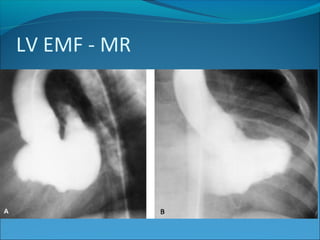

Angiography

Traditionally, angiography has been considered the

criterion standard when making the diagnosis of EMF.

Left and right ventriculography exhibits distortion of

chamber morphology by fibrosis and obliteration and

variable degrees of mitral and tricuspid regurgitation.

The mushroom sign has been used to describe the

shape of the affected ventricle when the apex is

obliterated completely by fibrosis.

Angiocardiography

Features of LV EMF –

1) Irregular outline of endocardium

2)Filling defects

3)Mitral regurgitation

4)Reduced EF

LV EMF - MR